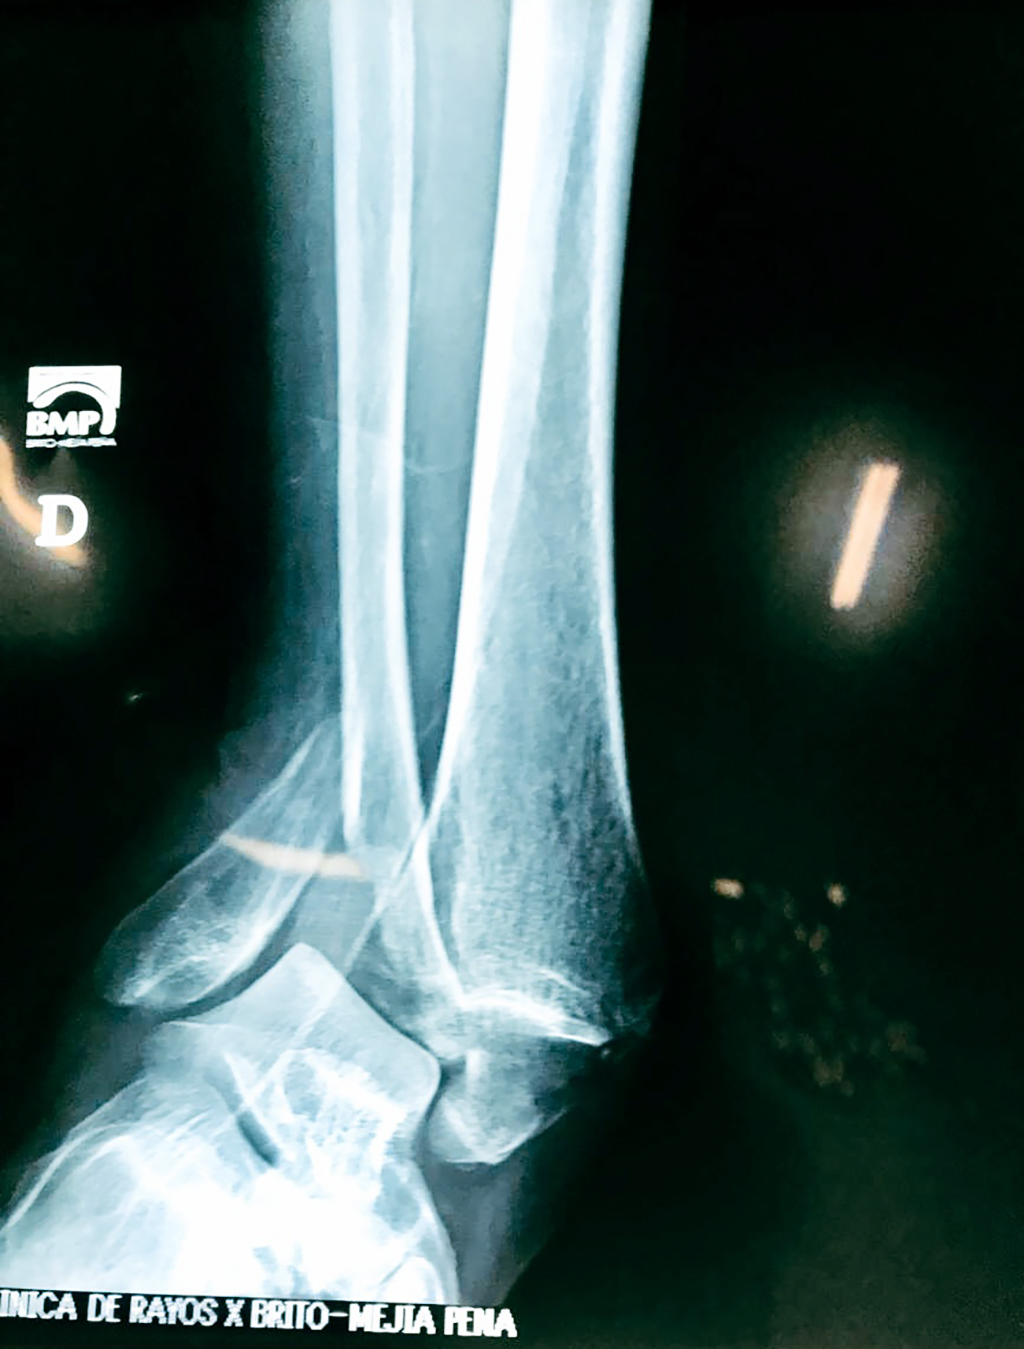

Una fractura de tobillo es la rotura de uno o más de los huesos del tobillo. Estas fracturas pueden ser:

Algunas fracturas de tobillo pueden requerir cirugía si:

- Los extremos de los huesos están desalineados entre sí (desplazados).

Cuando se necesita cirugía, es probable que esta implique el uso de clavijas de metal, tornillos o placas para sostener los huesos en su lugar mientras la fractura se consolida. Los elementos de soporte pueden ser temporales o permanentes.